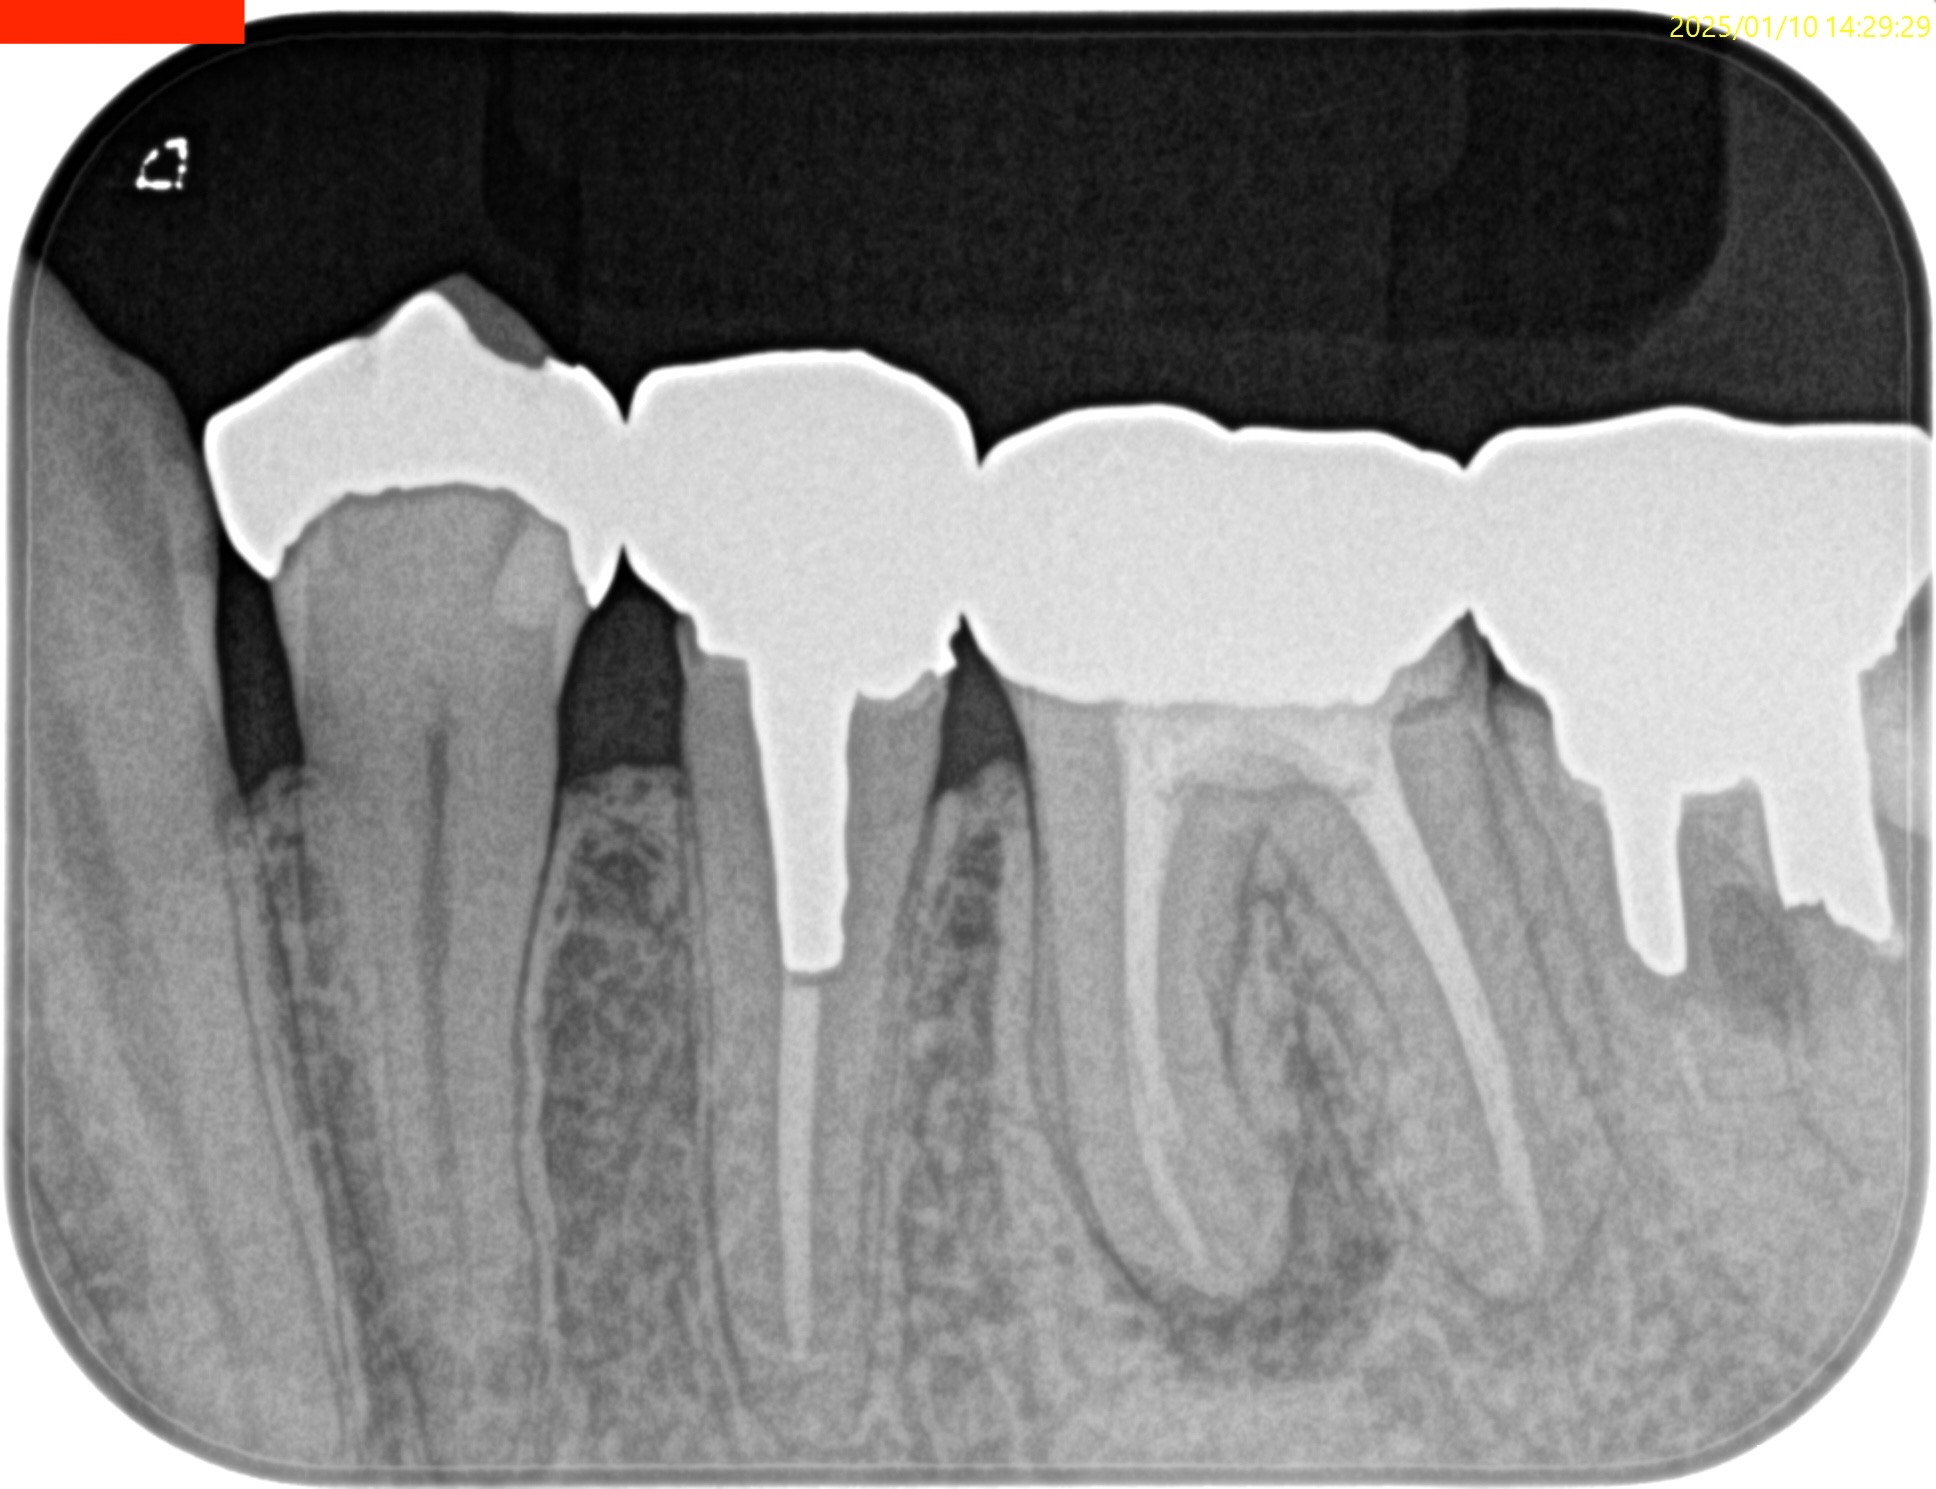

Pre-op PA(2025.1.10)

Pre-op CBCT(2025.1.10)